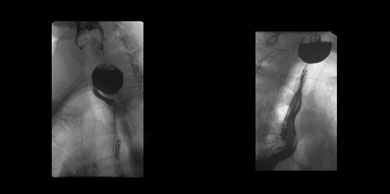

A videoesophagram is the most effective way to diagnose a Zenker's diverticulum. The barium used in the procedure fills the pouch, making it visible in the upper part of the esophagus, as shown in the picture below.